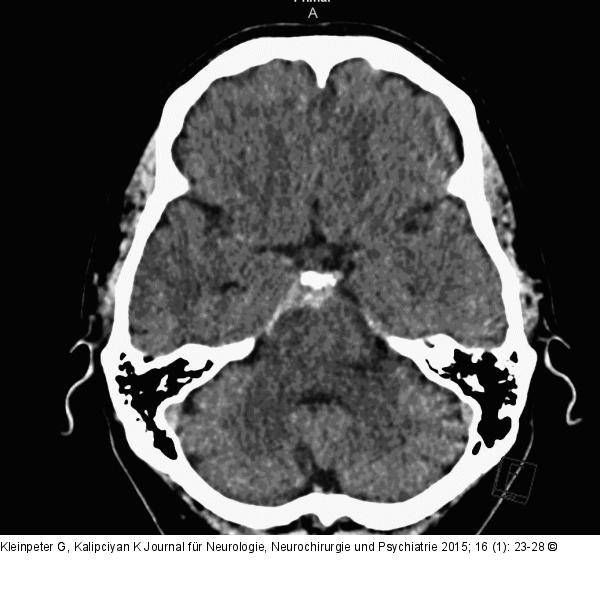

Abbildung 2: Subarachnoidalblutung Perimesenzephale Subarachnoidalblutung (pSAB). |

Perimesenzephale Subarachnoidalblutung (pSAB). |